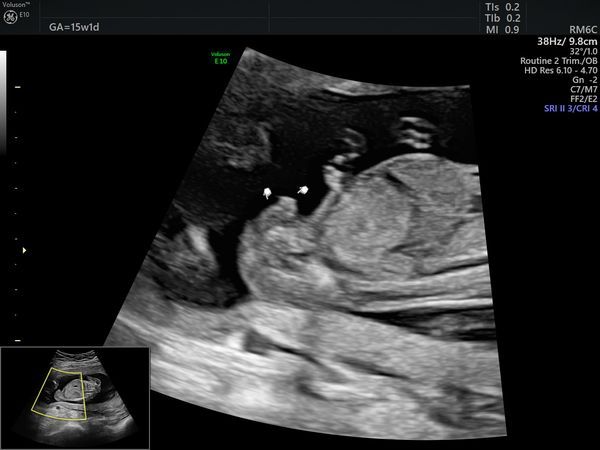

После скрининга пациентка пришла на УЗИ в 15 недель и 1 день. По УЗИ определялся один плод мужского пола, размеры плода пропорциональные, соответствовали менструальному сроку. Вес — 121 г (52 процентиль — норма). Пороков развития на момент исследования не было выявлено.

Плацента была расположена высоко от области внутреннего зева, структура не изменена. Количество околоплодных вод в норме. Длина шейки матки 35 мм (норма).